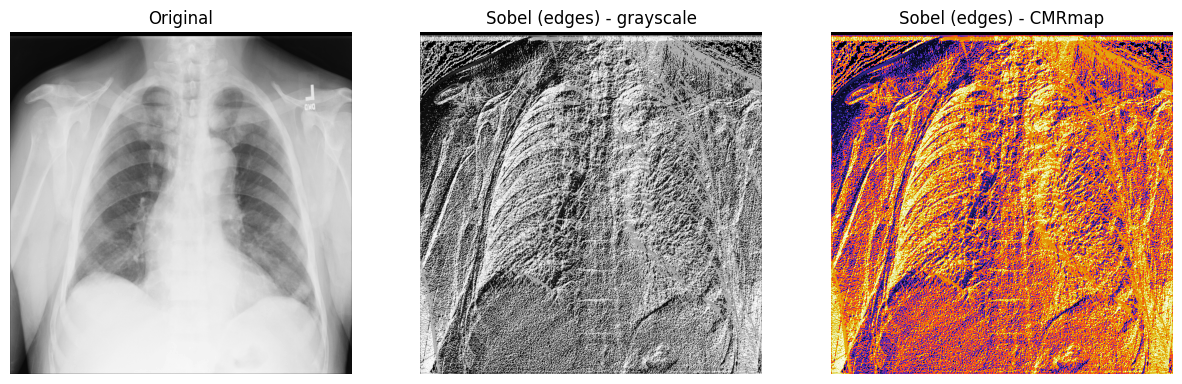

Sobel-Feldman 算子(Sobel 滤波器)

为了在二维 X 射线图像的水平和垂直轴上找到高空间频率区域(边缘或边缘图),可以使用 Sobel-Feldman 算子(Sobel 滤波器)技术。Sobel 滤波器将两个 3x3 的卷积核矩阵(一个用于每个轴)应用于 X 射线图像,然后使用勾股定理将这两个点(梯度)组合起来产生梯度幅度。

1. 使用 Sobel 滤波器(scipy.ndimage.sobel())对 X 射线图像的 x 轴和 y 轴进行滤波。然后,使用勾股定理和 NumPy 的 np.hypot() 计算 x 和 y 之间的距离,以获得幅度。最后,将重新缩放的图像归一化,使像素值介于 0 和 255 之间。

图像归一化 遵循 output_channel = 255.0 * (input_channel -min_value) / (max_value - min_value) 公式。由于使用的是灰度图像,只需对一个通道进行归一化。

x_sobel = ndimage.sobel(xray_image, axis=0)

y_sobel = ndimage.sobel(xray_image, axis=1)

xray_image_sobel = np.hypot(x_sobel, y_sobel)

xray_image_sobel *= 255.0 / np.max(xray_image_sobel)

2. 将新图像数组的数据类型从 float16 更改为 32 位浮点格式,以与 Matplotlib 兼容:

print("更改前的数据类型:", xray_image_sobel.dtype)

xray_image_sobel = xray_image_sobel.astype("float32")

print("更改后的数据类型:", xray_image_sobel.dtype)

更改前的数据类型: float16

更改后的数据类型: float32

3. 显示原始 X 射线图像和应用 Sobel “边缘”滤波器的图像。注意,这里使用了灰度和 CMRmap 颜色映射来帮助强调边缘:

fig, axes = plt.subplots(nrows=1, ncols=3, figsize=(15, 15))

axes[0].set_title("原始图像")

axes[0].imshow(xray_image, cmap="gray")

axes[1].set_title("Sobel(边缘)- 灰度")

axes[1].imshow(xray_image_sobel, cmap="gray")

axes[2].set_title("Sobel(边缘)- CMRmap")

axes[2].imshow(xray_image_sobel, cmap="CMRmap")

for i in axes:

i.axis("off")

plt.show()